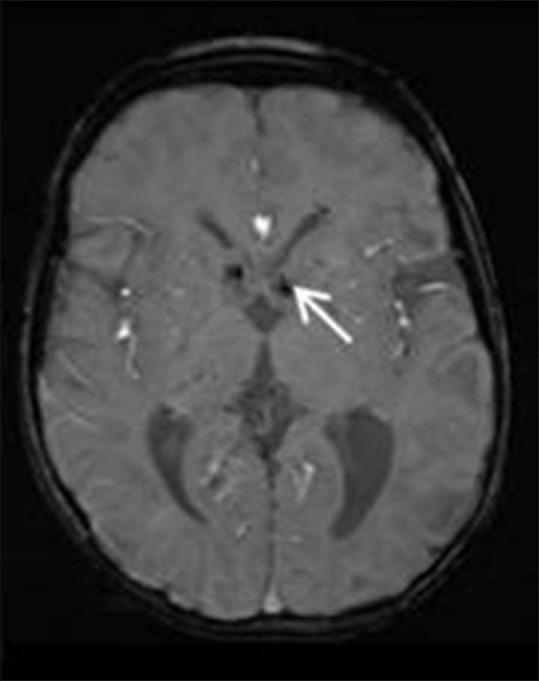

phakomatoses:图文综述。

Phakomatoses: A pictorial review.

Phakomatoses or Neurocutaneous syndromes are a heterogeneous group of disorders and have variable inheritance pattern. Currently, more than 30 entities are included in this group. These disorders primarily affect the central nervous system; however, skin, viscera, and other connective tissues can also be involved with variable clinical presentation. We will describe and illustrate the various radiological findings of the common entities through the iconography of the cases presented to our department.

摘要

phakomatoses或神经皮肤综合征是一组异质性疾病,具有可变的遗传模式。目前,该组包括30多种疾病。这些疾病主要影响中枢神经系统;然而,皮肤、内脏和其他结缔组织也可能受累,临床表现各异。我们将通过提交至我科病例的影像学表现来描述和说明常见疾病的各种放射学表现。